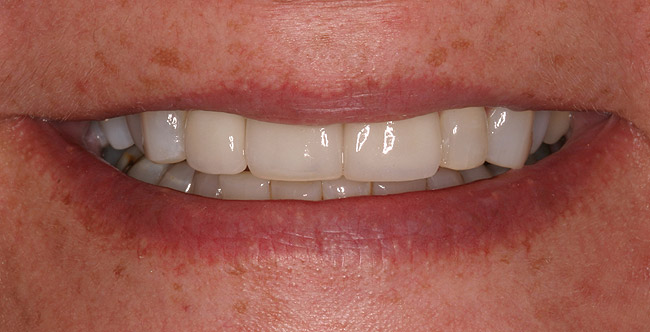

Figure 5a  Congenitally missing lateral incisors. Postorthodontic therapy, prior to implant placement.

Figure 5a

Figure 5b  Congenitally missing lateral incisors. Postorthodontic therapy, prior to implant placement.

Figure 5b